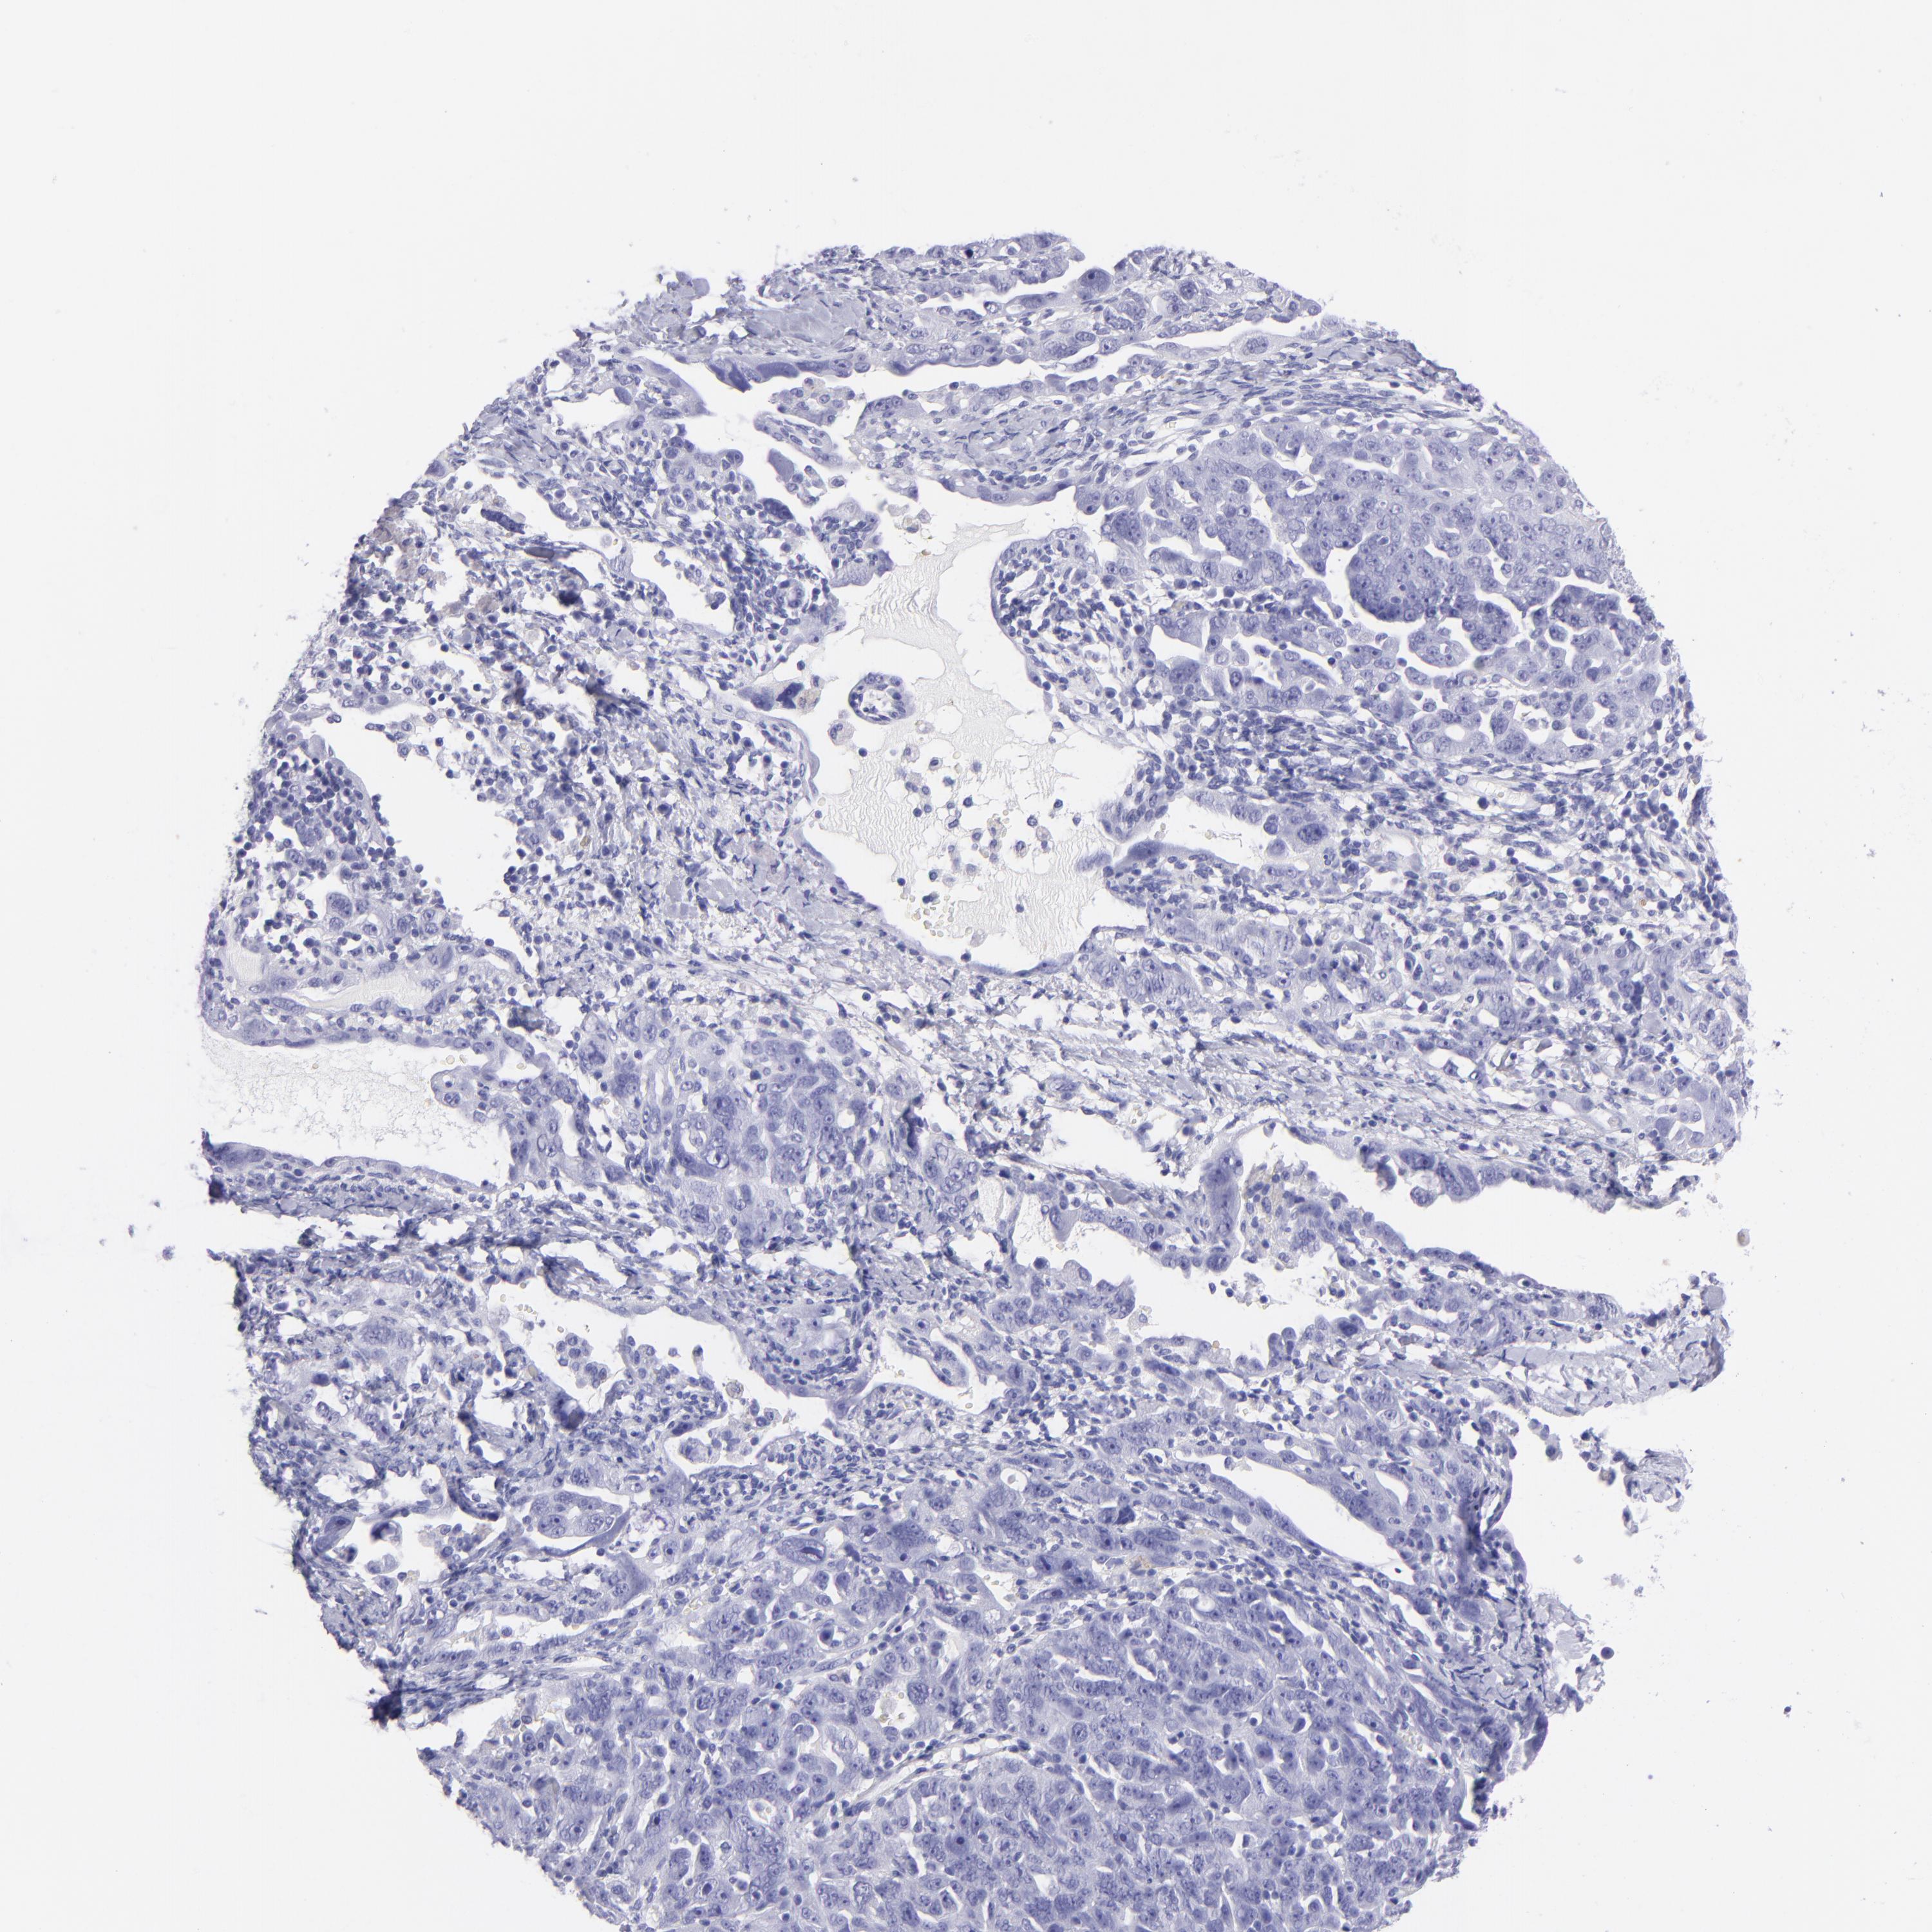

OVARIAN CANCER - Protein expressioni

A mouse-over function shows sample information and annotation data. Click on an image to view it in a full screen mode. Samples can be filtered based on level of antibody staining by selecting one or several of the following categories: high, medium, low and not detected. The assay and annotation is described here.

Note that samples used for immunohistochemistry by the Human Protein Atlas do not correspond to samples in the TCGA dataset.

Antibody stainingi

Antibody staining in the annotated cell types in the current human tissue is reported as not detected, low, medium, or high, based on conventional immunohistochemistry profiling in selected tissues. This score is based on the combination of the staining intensity and fraction of stained cells.

Each image is clickable and will lead to virtual microscopy that enables deeper exploration of all samples and also displays staining intensity scores, fraction scores and subcellular localization as well as patient and tissue information for each sample.

Antibody HPA009177

Antibody CAB002661

Staining

High

Medium

Low

Not detected

Intensity

Strong

Moderate

Weak

Negative

Quantity

>75%

75%-25%

<25%

None

Location

Nuclear

Cytoplasmic/membranous

Cytoplasmic/membranous,nuclear

Cystadenocarcinoma, serous, NOS

Carcinoma, endometroid

Cystadenocarcinoma, mucinous, NOS

Carcinoma, NOS